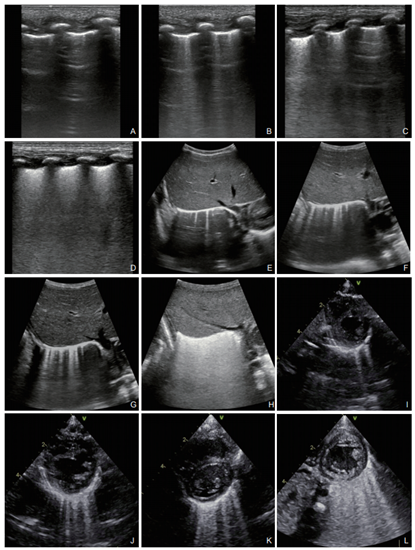

在过去几年里,肺部超声成像在临床上的应用越来越多,从传统的仅能判断胸腔积液的有无和多少,已经革命性地走向了肺实质成像检查。我们仅需一个简单的3~5分钟肺部超声检查,便可以对90%以上病例中的5种最常见急性呼吸衰竭重症病因(肺水肿、肺炎、肺栓塞、COPD、气胸)作出诊断。当肺部发生疾病时,间质的渗出造成肺泡和间质含水比例变化,也就是说一部分肺组织可以被超声穿透了。不同的气、水比例,不同的图像表现,产生一系列有规律的超声征象变化,由此,肺超声检查成像理论与诊断依据便产生了。

图示:不同含水量肺脏超声声像图